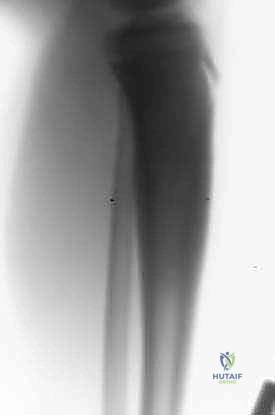

المرحلة الخامسة: التثبيت والإغلاق (Fixation and Closure)

يتم تثبيت الشظية المزروعة بقوة مع نهايات العظم الأصلي باستخدام شرائح معدنية ومسامير أو مثبتات خارجية. يضمن هذا التثبيت الميكانيكي استقرار العظم حتى يكتمل الالتئام البيولوجي.

من الأسبوع السادس إلى الشهر الثالث: التحميل الجزئي

- بناءً على صور الأشعة السينية التي تؤكد بدء التئام العظم المنقول مع العظم الأصلي، يسمح الأستاذ الدكتور هطيف بالتحميل الجزئي التدريجي باستخدام العكازات.

- العظم المنقول (الشظية) يبدأ في التضخم (Hypertrophy) استجابة للوزن المحمل عليه، ليصبح تدريجياً في سماكة وقوة العظم الأصلي المفقود.